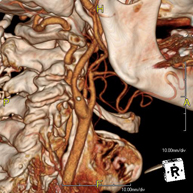

Prueba radiológica que consiste en obtener imágenes del hueso peñasco del temporal (oído interno, medio y externo) de alta definición anatómica mediante el empleo de un equipo de TC (Tomografía Computarizada). Indicaciones: pérdida de audición súbita o crónica, cuadros vertiginosos, mareo, malformaciones congénitas. - Angio – TC Troncos Supraaórticos

Prueba radiológica que consiste en obtener imágenes de las arterias carótidas del cuello de alta definición anatómica mediante el empleo de un equipo de TC (Tomografía Computarizada) y la inyección de contraste intravenoso. Posteriormente, las imágenes son reconstruidas en tres dimensiones (3D). Indicaciones: accidente vascular cerebral agudo, accidente vascular transitorio, soplo carotídeo. - TC Columna cervical